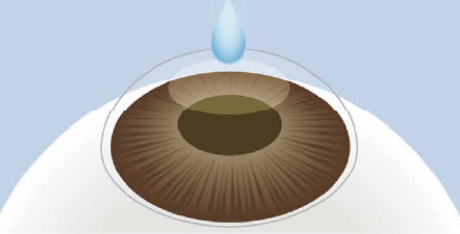

点眼麻酔

手術前に点眼麻酔を行い、

痛みを感じないようにします。